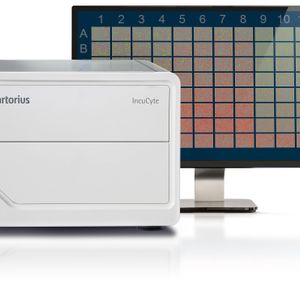

SEP 15, 2022Clinical & Molecular DXStaff shortages and increasing sample volume are the factors typically driving laboratories to assess their current work ...